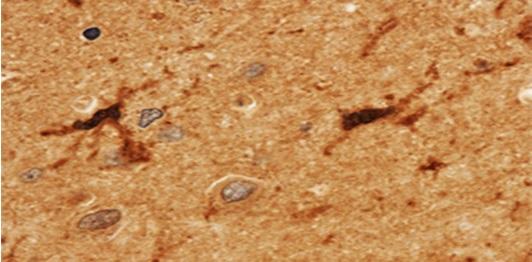

Figure-1:Immunohistochemical analysis of Human/Mouse TLR2 (Clone : mT2.7) in human spleen tissue by using 1:50 dilution of anti-TLR2 antibody.

Monoclonal antibody 10-3507 reacts with mouse Toll-like receptor 2 (TLR2, CD282). Toll-like receptors (TLR) are highly conserved throughout evolution and have been implicated in the innate defense to many pathogens. In Drosophila toll is required for the anti-fungal response, while the related 18-wheeler is involved in antibacterial defenses. In mammals, TLR identified as type I transmembrane signaling receptors with pattern recognition capabilities, have been implicated in the innate host defense to pathogens. TLR2 has been identified as a receptor that is central to the innate immune response to lipoproteins of Gram-negative bacteria, several whole Gram-positive bacteria, as well as a receptor for peptidoglycan and lipoteichoic acid and other bacterial cell membrane products. A functional interaction between TLR2 and TLR6 in the cellular response to various bacterial products has been discovered. The currently accepted paradigm regards TLR2 as an essential receptor for many eubacterial cell wall components, including lipoproteins and peptidoglycan. Bacterial species as diverse as mycobacteria, spirochetes, mycoplasma, Staphylococcus aureus, and Streptococcus pneumoniae have all been shown to mediate cellular activation via TLR2. The monoclonal antibody mT2.7 stained overexpressed, as well as endogenous cell surface- and intracellular TLR2. The antibody does not affect cell activation through TLR2.

The monoclonal antibody 10-3507 can be used for flow cytometry and immunohistology on frozen sections. Furthermore the antibody is useful for immuno assays and immuno precipitation. The antibody does not affect cell activation through TLR2 (CD282).

Tissue Specificity: | Detected in a macrophage cell line, smooth muscle, lung, spleen, thymus, brain and adipose tissue. Cell surface expression detected in lung alveolar macrophages, dendritic macrophages and at lower levels in lung macrophages (at protein level) (PubMed:19362712). |